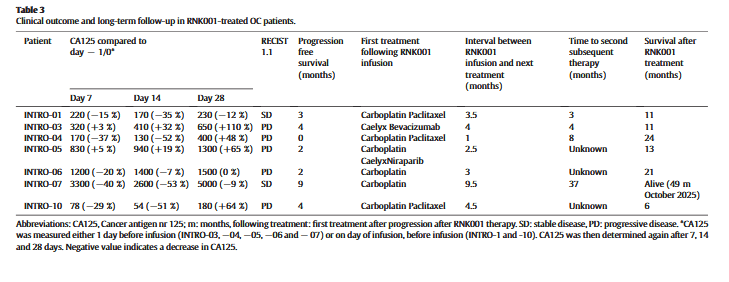

在RNK001输注时,所有患者的CA125水平均升高(表1)。在七分之五的患者(71%)中,我们观察到CA125水平在第7天下降了15-40%,在第14天下降了7-53%(表3,图3A)。在第28天,七分之二的患者仍显示出9-12%的下降,但其他患者显示出逐渐增加。根据RECIST 1.1标准,两名患者(INTRO-01和-07)病情稳定;然而,五名患者(包括接受Cy/Flu化疗的INTRO-10)在RNK001输注后不久出现了疾病进展(表3)。大多数患者在输注后1至4.5个月开始姑息性化疗,腹膜肿瘤病变1在3个月时显著减少至19mm(减少50%),在6个月时减少至14mm(减少63%)(图3C)。此外,较小的肝肿瘤病变2从基线时的37毫米减少到3个月时的23毫米(减少38%)和6个月时为19毫米(减少49%)。在较大的肝肿瘤病变3中没有观察到重大变化。在9.5个月时,疾病进展,该患者接受了顺铂、吉西他滨和贝伐单抗治疗,反应非常好,在输注RNK001后42个月,她仍然活着。接受RNK001治疗的患者的平均OS为18个月。